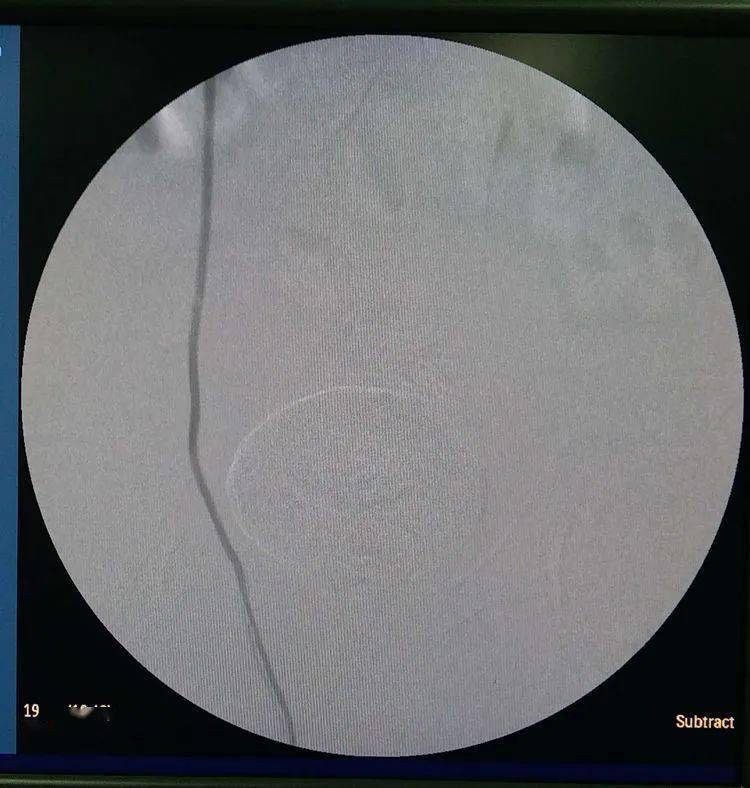

当囊肿内核膀胱内均有造影剂充盈时,囊肿表现为圆形或椭圆形密度增高

阴茎背深静脉白膜下包埋术——让幸福不再流失